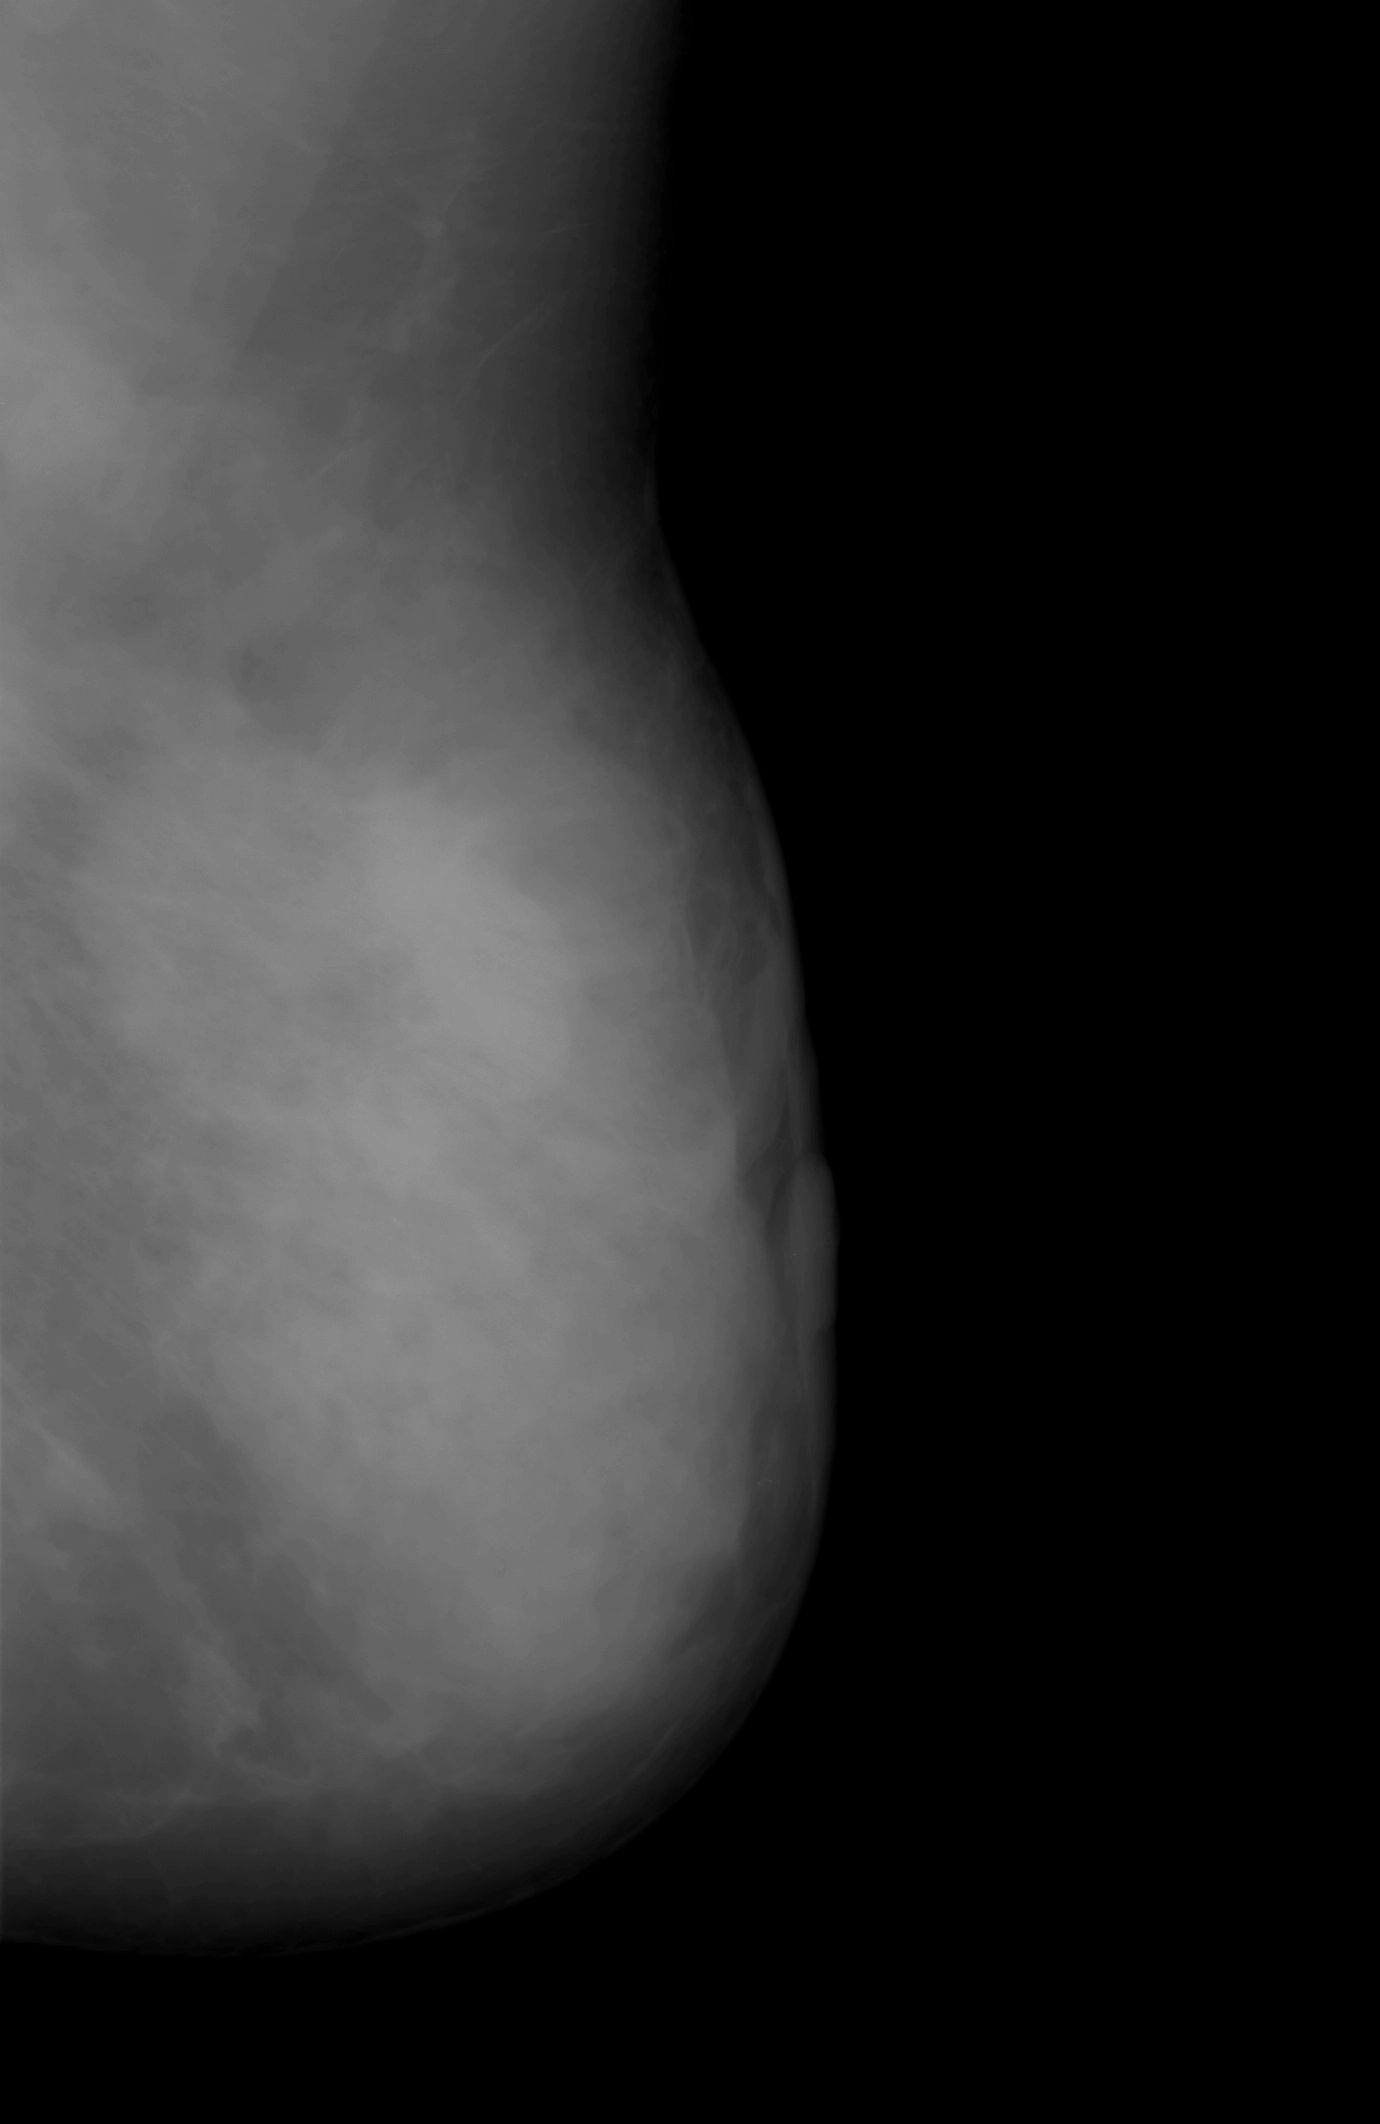

Ung thư biểu mô tuyến vú dạng viêm (Inflammatory carcinoma of the breast)